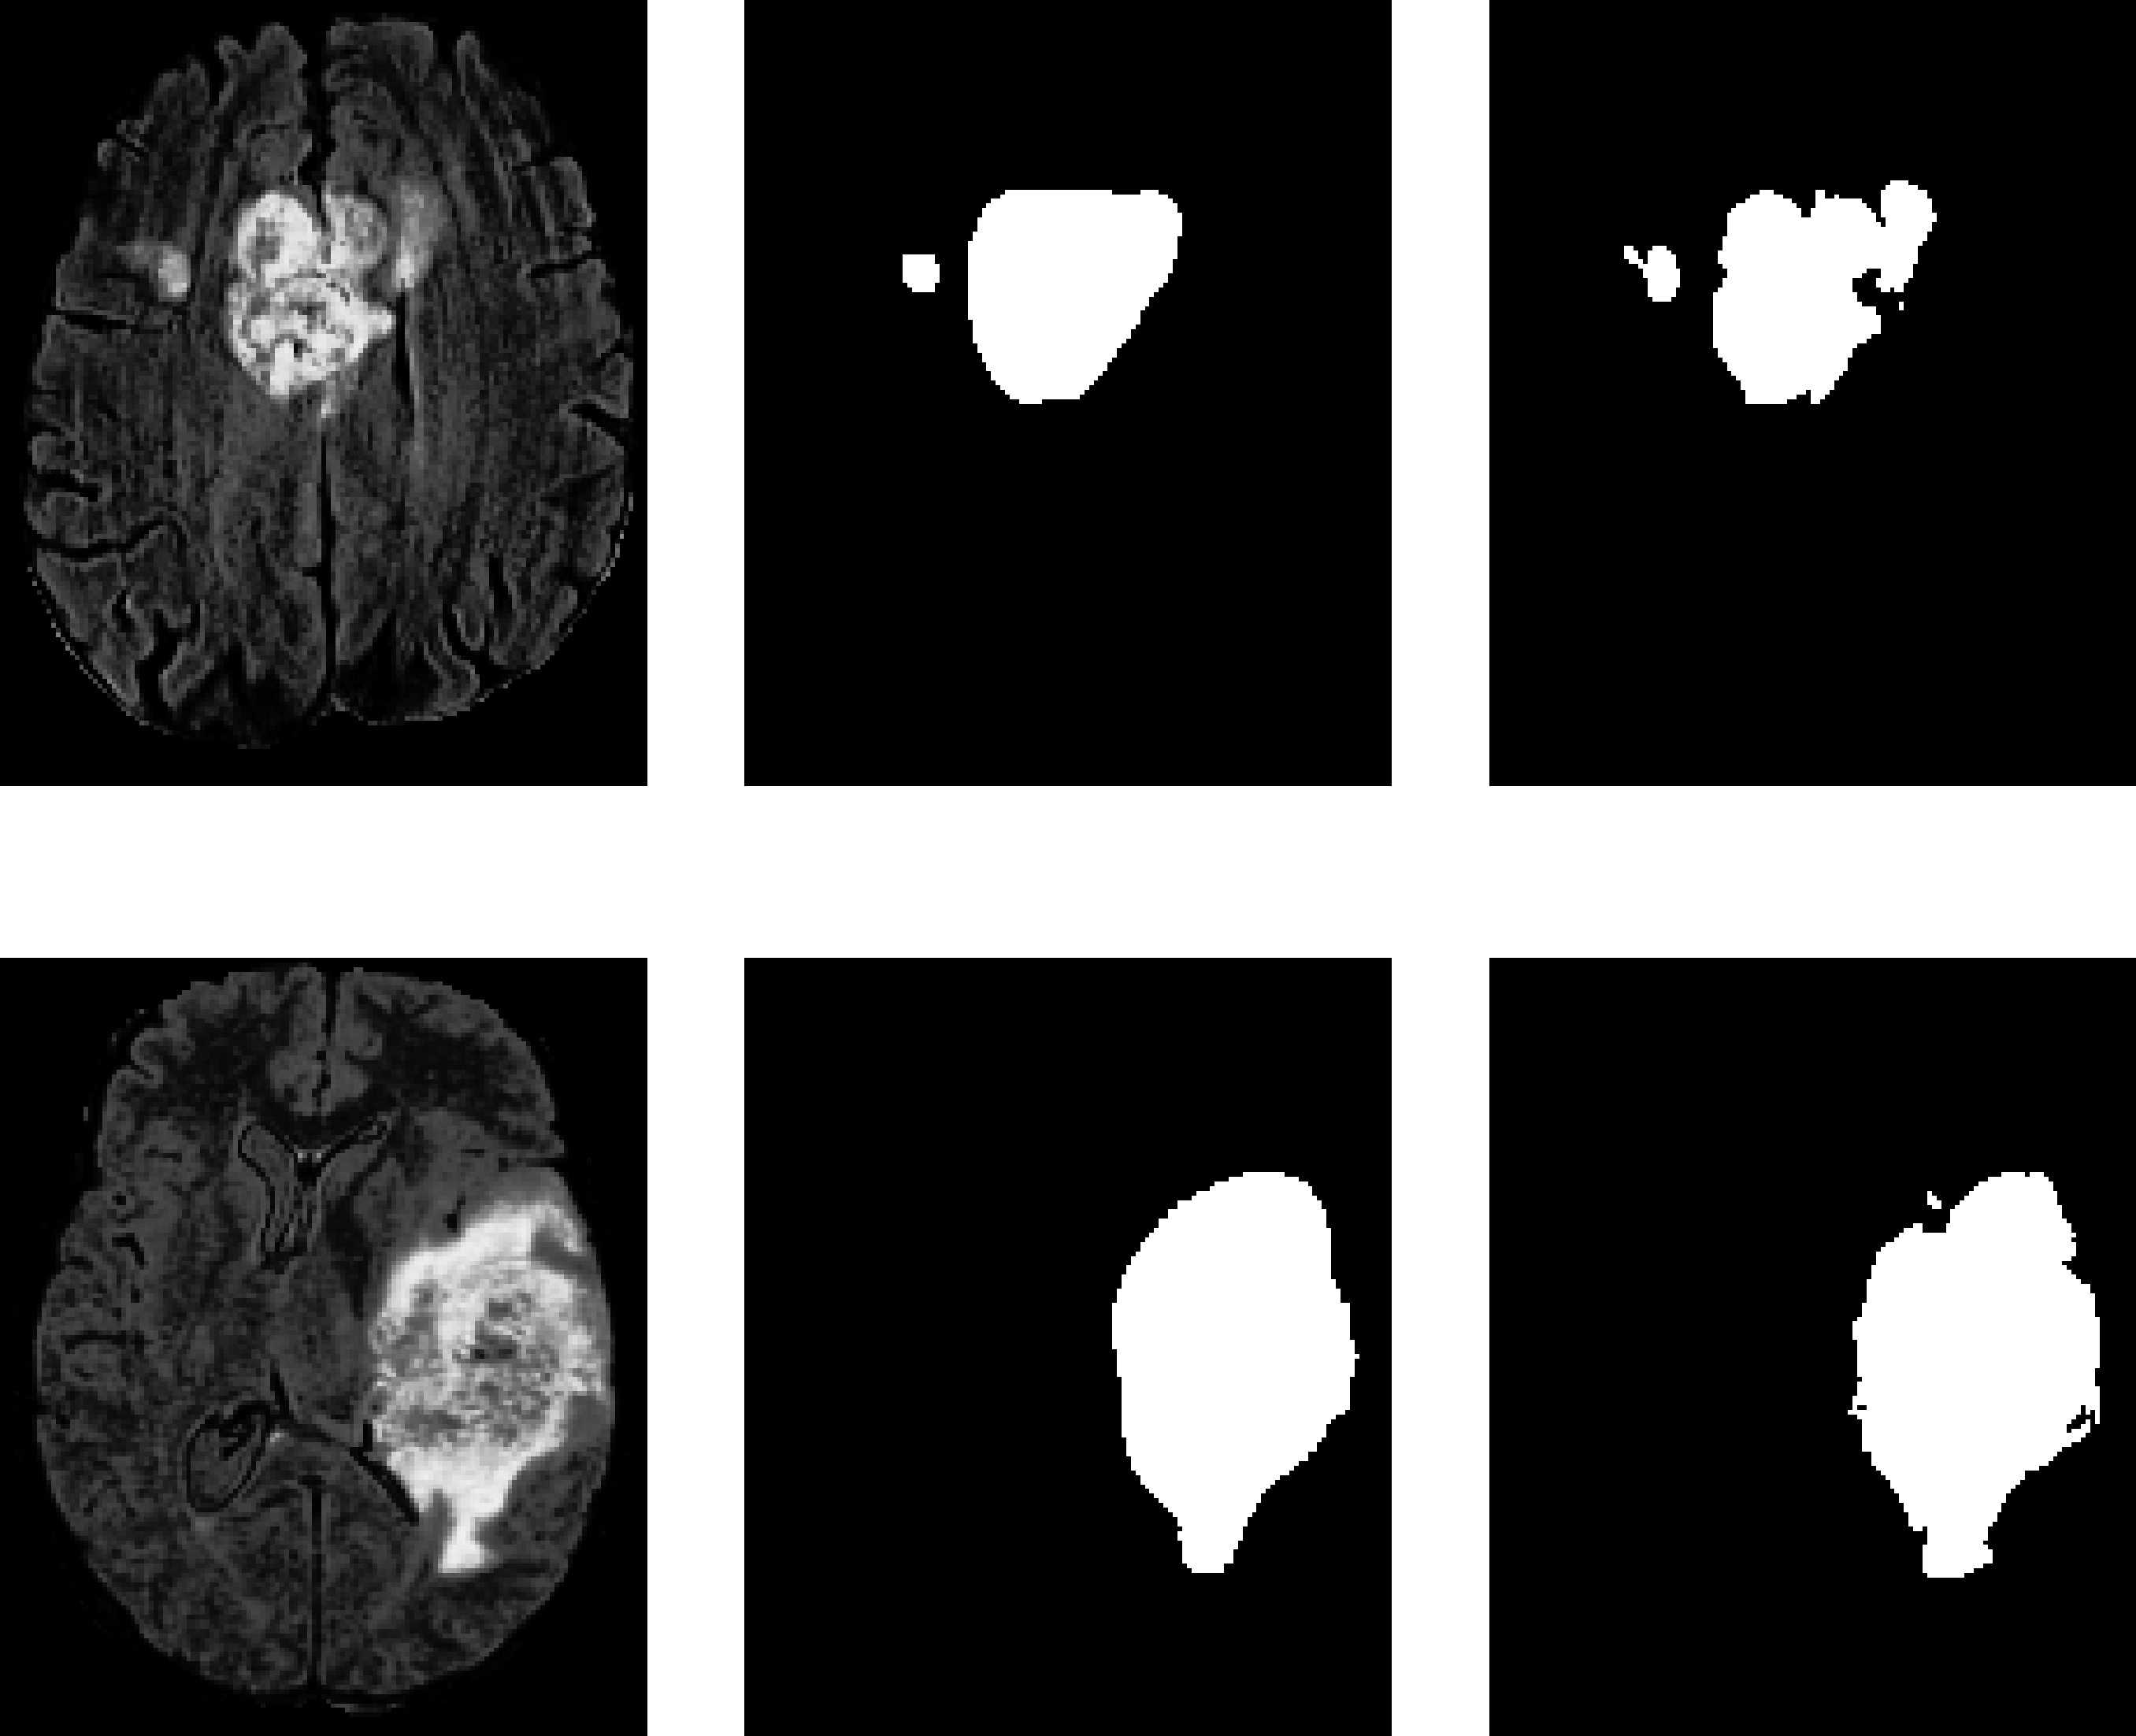

Examples of cancerous MR images and their generated non-cancerous variants are presented in Figure 5. Examples of cancerous MR images, their generated segmentations, and their true segmentations are visualized in Figure 6.

Refer to caption

(a) Examples from BraTS dataset.

(b) Examples from PLGNT dataset.

Fig. 6: MR image FLAIR channel (left), model segmentation (middle), true segmentation (right).